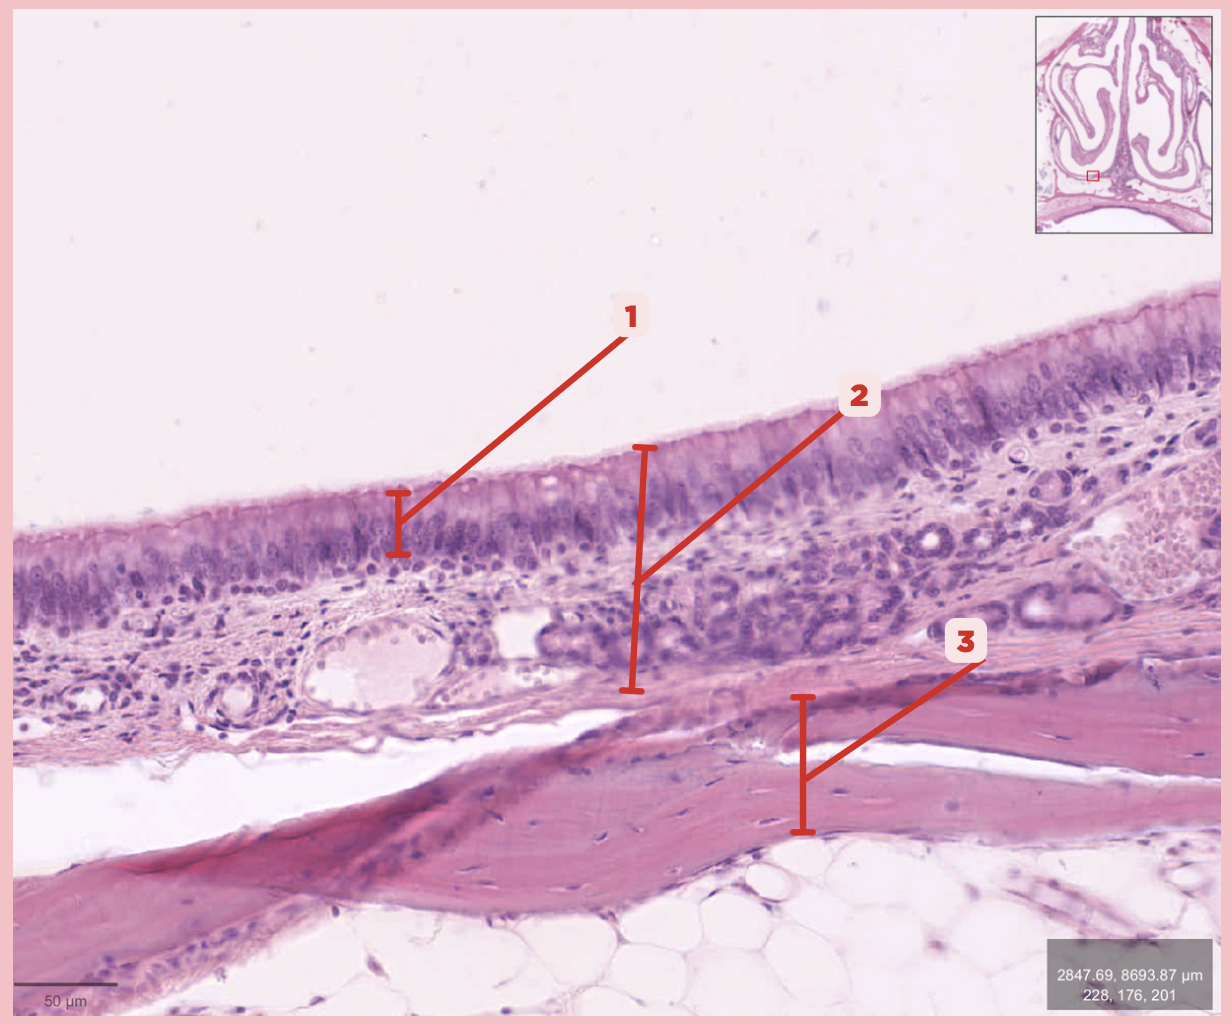

Respiratory Epithelium

Identify the structure labeled as 1.

Mucosa

Identify the structure labeled as 2.

Bone

Identify the structure labeled as 3.

Keratinized stratified squamous epithelium

What’s the lining epithelium at #3?

No

Are Glands present at #1?

Lamina Propria

Identify the structure labeled as 1.

Adipocytes

Identify the structure labeled as 2.

Keratinized stratified squamous epithelium

Identify the structure labeled as 3.